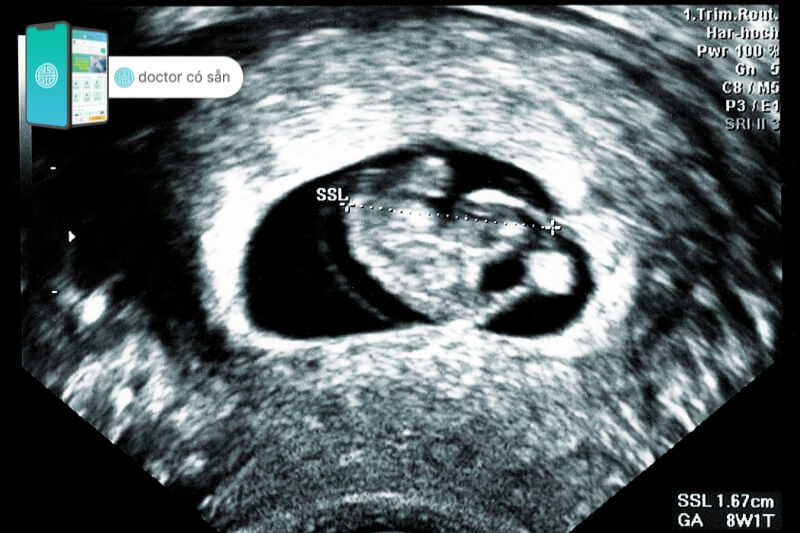

Thai 3 tuần tuổi siêu âm được không?

Một câu hỏi phổ biến mà nhiều phụ nữ đặt ra là liệu có thể thực hiện siêu âm thai để kiểm tra khi thai 3 tuần tuổi hay không?

Thực tế khi có thai 3 tuần, trứng đã thụ tinh và đang trong quá trình di chuyển tới tử cung để làm tổ. Trong giai đoạn này các phôi thai còn rất nhỏ do đó kết quả siêu âm thường không thể hiển thị được hình ảnh thai.

Đây là giai đoạn quá sớm để thấy bất kỳ dấu hiệu thai nhi nào và thậm chí siêu âm đầu dò cũng không thể hiển thị hình ảnh thai có thể ảnh hưởng đến sức khỏe của thai nhi nếu mẹ bầu thực hiện.

Thai 3 tuần tuổi siêu âm có thấy không?

Thai 3 tuần tuổi vẫn ở giai đoạn đầu của sự phát triển và tồn tại dưới dạng phôi thai. Vì cơ thể của nó vẫn rất nhỏ và chưa hình thành hình dạng rõ ràng nên không thể quan sát hình ảnh của phôi thai này bằng mắt thường hoặc thông qua siêu âm.